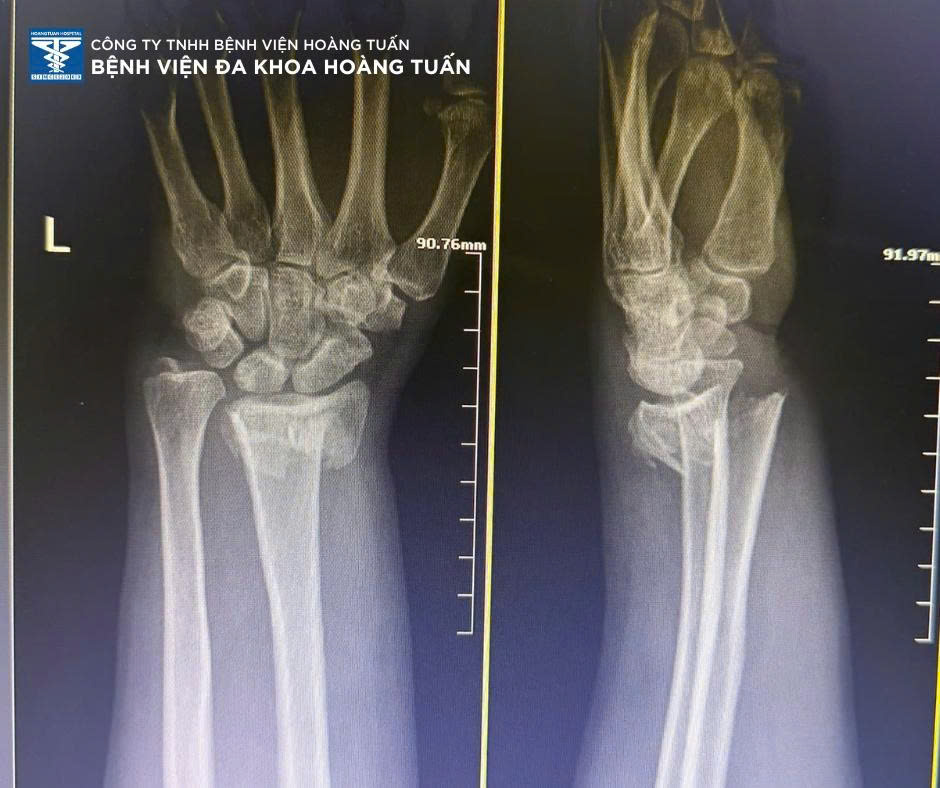

Một trường hợp khác tương tự, bệnh nhân nữ 57 tuổi, tai nạn sinh hoạt tại nhà sưng đau nhiều vùng cẳng tay phải, được người nhà đưa đến khám tại Bệnh viện Đa khoa Hoàng Tuấn.

Sau thăm khám và chụp X-quang kiểm tra, BSCKI. Vũ Quốc Dũng – Khoa Ngoại CTCH Bệnh viện Đa khoa Hoàng Tuấn nhận định bệnh nhân đã gãy đầu dưới 2 xương cẳng tay phải, cần phẫu thuật kết hợp xương điều trị sớm. Ekip phẫu thuật Bệnh viện Đa khoa Hoàng Tuấn nhanh chóng chuẩn bị bệnh nhân và tiến hành thực hiện sớm. Sau phẫu thuật bệnh nhân vận động nhẹ, giảm sưng đau, đang trong thời gian phục hồi vận động và theo dõi tiến triển.